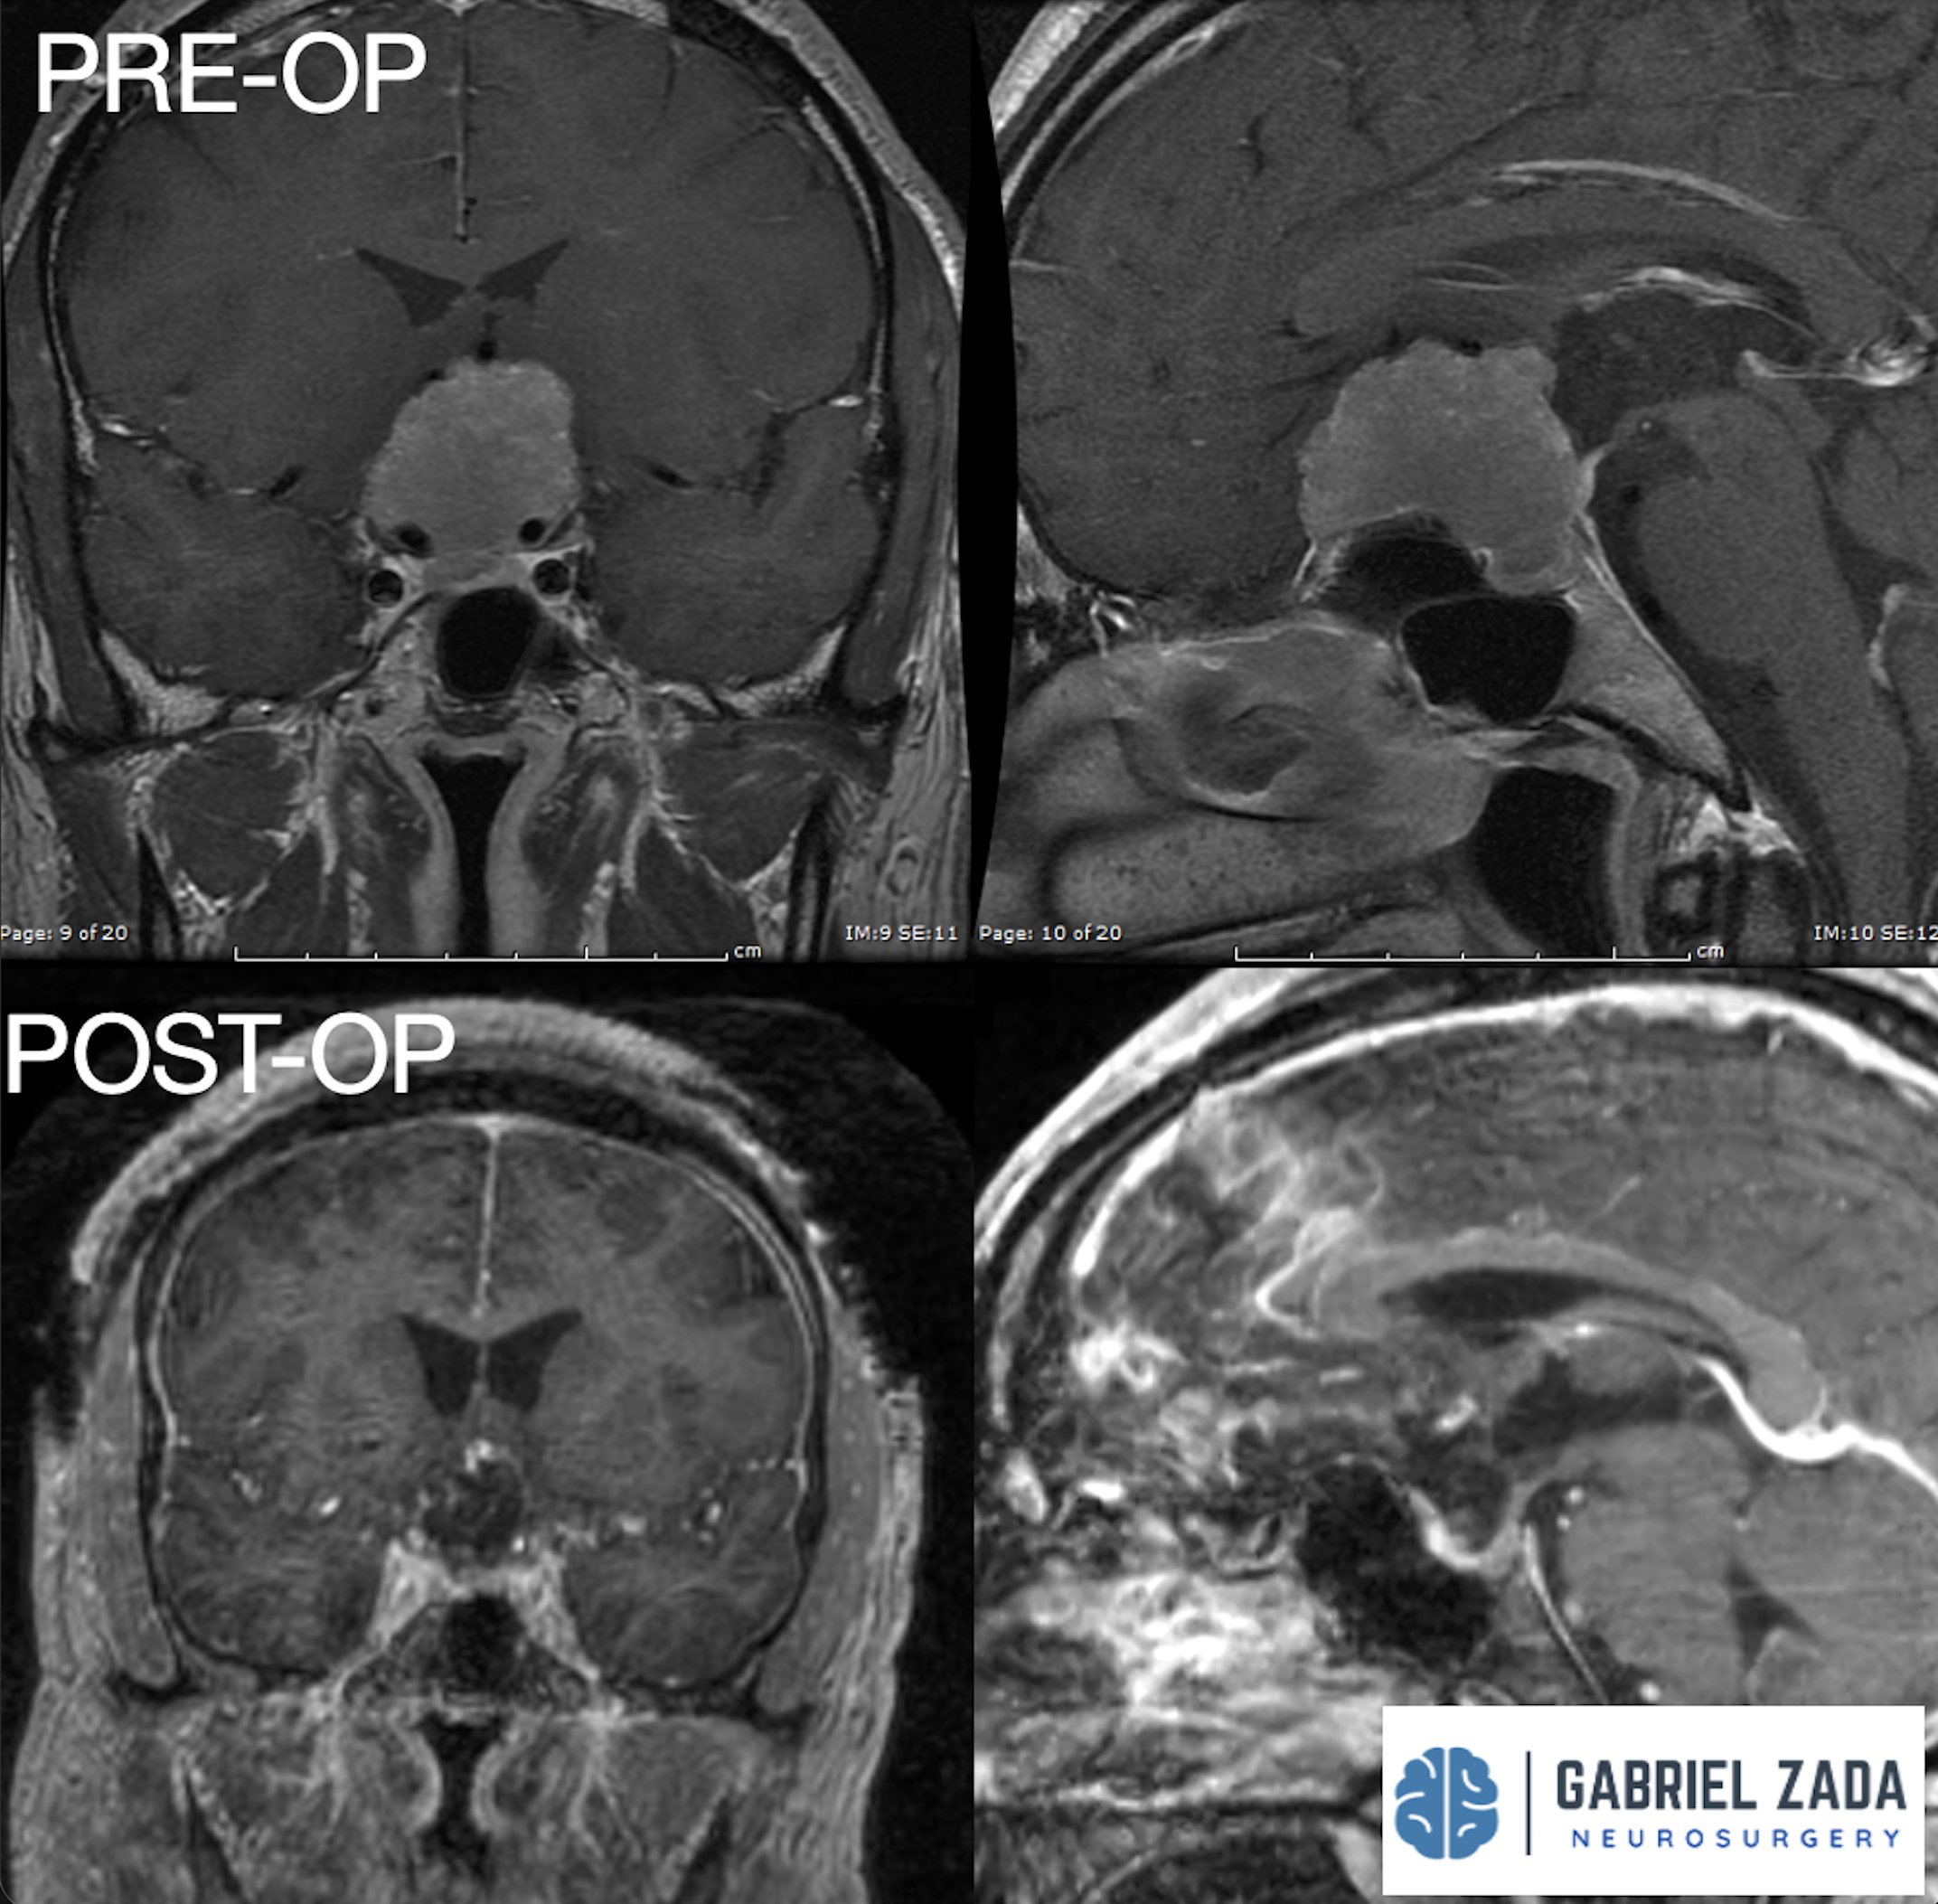

Explore this comprehensive gallery featuring pre‑ and post‑operative imaging of patients with skull‑base tumors treated by Gabriel Zada, MD, MS, FAANS, FACS. These cases highlight Dr. Zada’s expertise in advanced neurosurgical techniques and outcomes.

*Representative cases shown for educational purposes. All images de-identified. Individual results vary.